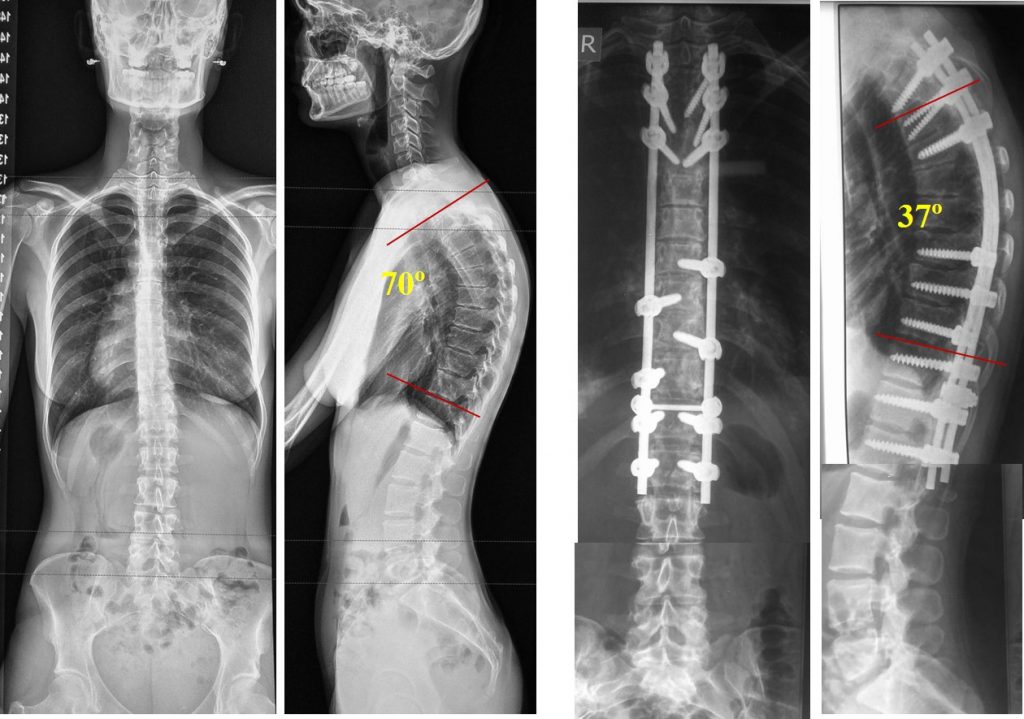

Медицинские снимки: рентген позвоночника сбоку